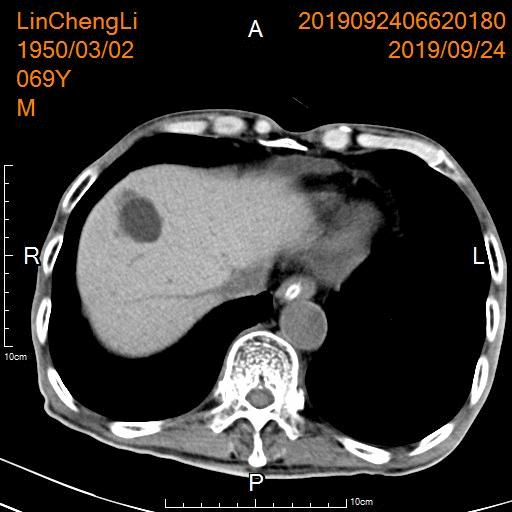

- 复查CT显示胃部肿瘤明显坏死

CT显示胃部肿瘤大片坏死灶

后续行胃部肿瘤区域化疗灌注治疗,病灶进一步缩小控制,腹痛、腹胀等临床症状缓解、改善。

CT显示胃部肿瘤明显缩小